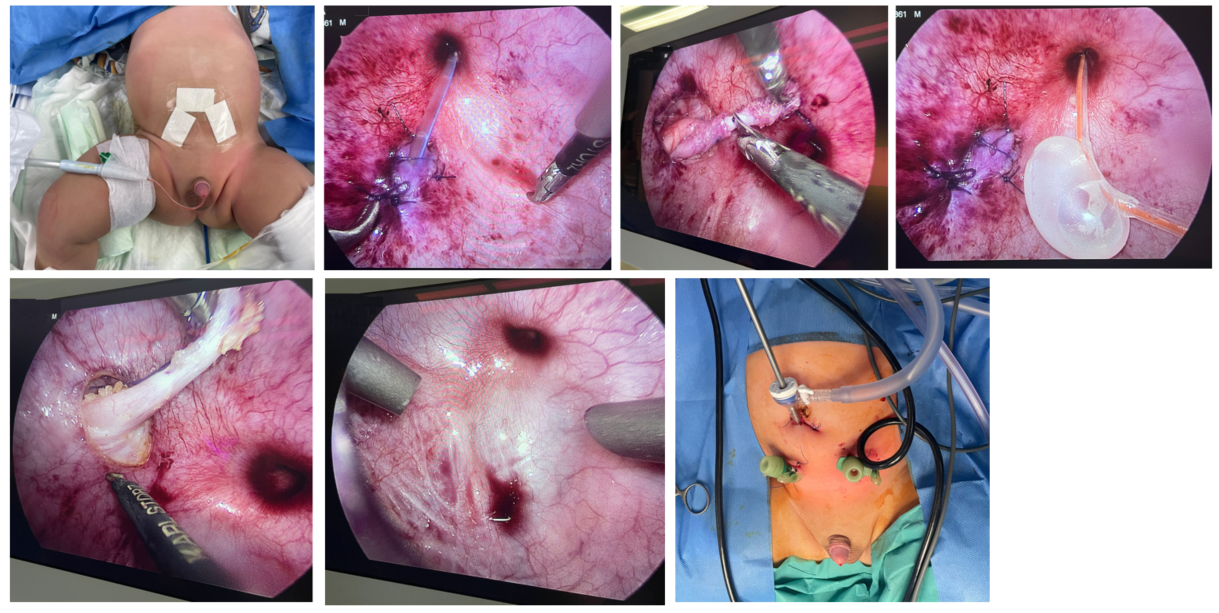

A 4 years old child with bilateral grade 4 Vesico-ureteric reflux and reflux nephropathy had Pneumo-Vesicoscopic ureteric reimplantation. Child had a very comfortable post operative period and discharged on 3rd post op day. This procedure is a paradigm shift from the conventional open cross trigonal ureteric reimplantation where a Pfannensteil (lower transverse) incision is usually made , bladder is opened and post surgery ureteric catheters are exteriorized per abdomen, requiring 7-10 days of postop recovery ,significant amount of analgesia, leaving a large scar; or conventional Laparoscopic extra vesical reimplantation ( not always suitable for dilated high grade refluxing ureters). In this procedure all the reimplantaion steps were carried out entirely within the domain of Urinary bladder by 3mm minilaparoscopic instruments , without any post op stents. The child had very comfortable recovery with minimal analgesia and left with barely appreciable scar.

This relatively new technique has tremendously improved the quality of life of the reimplantation kids